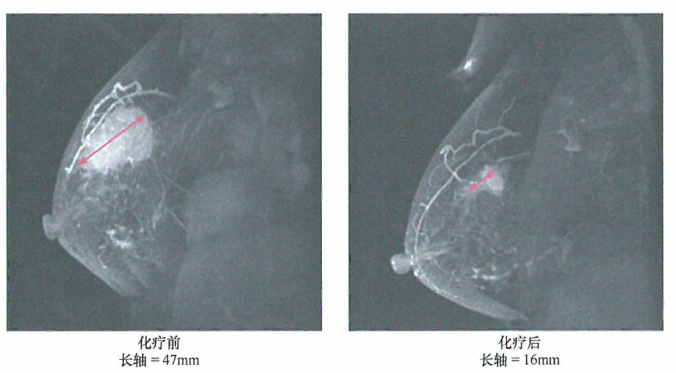

美国看病机构爱诺美康介绍,通过高分辨率、非侵袭性人体组织成像,磁共振成像(MRI)技术的发展使活体组织的非侵入性可视化的分辨率越来越高。现在的MRI可以检测到体积非常小的乳腺瘤(直径几毫米)。如图中所示,MRI可以用来详细观察抗肿瘤治疗的进展(在这一病例中使用的足蒽环类的细胞毒制剂进行化学治疗)。